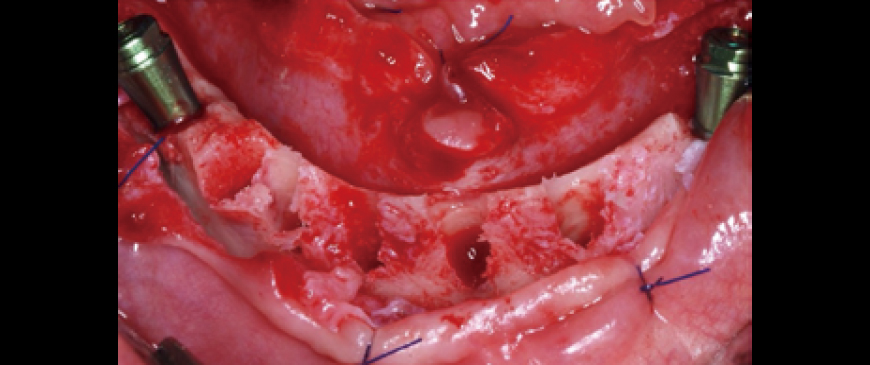

Fig 6

Four ARi implant fixtures were placed. A 5-6mm dehiscence occurred on the labial side, but it was limited to the machined cuff.

Fig 7

To prevent potential visibility through the thin biotype gingiva in the future, a layer of Ossix Volumax (10x40mm) was placed.